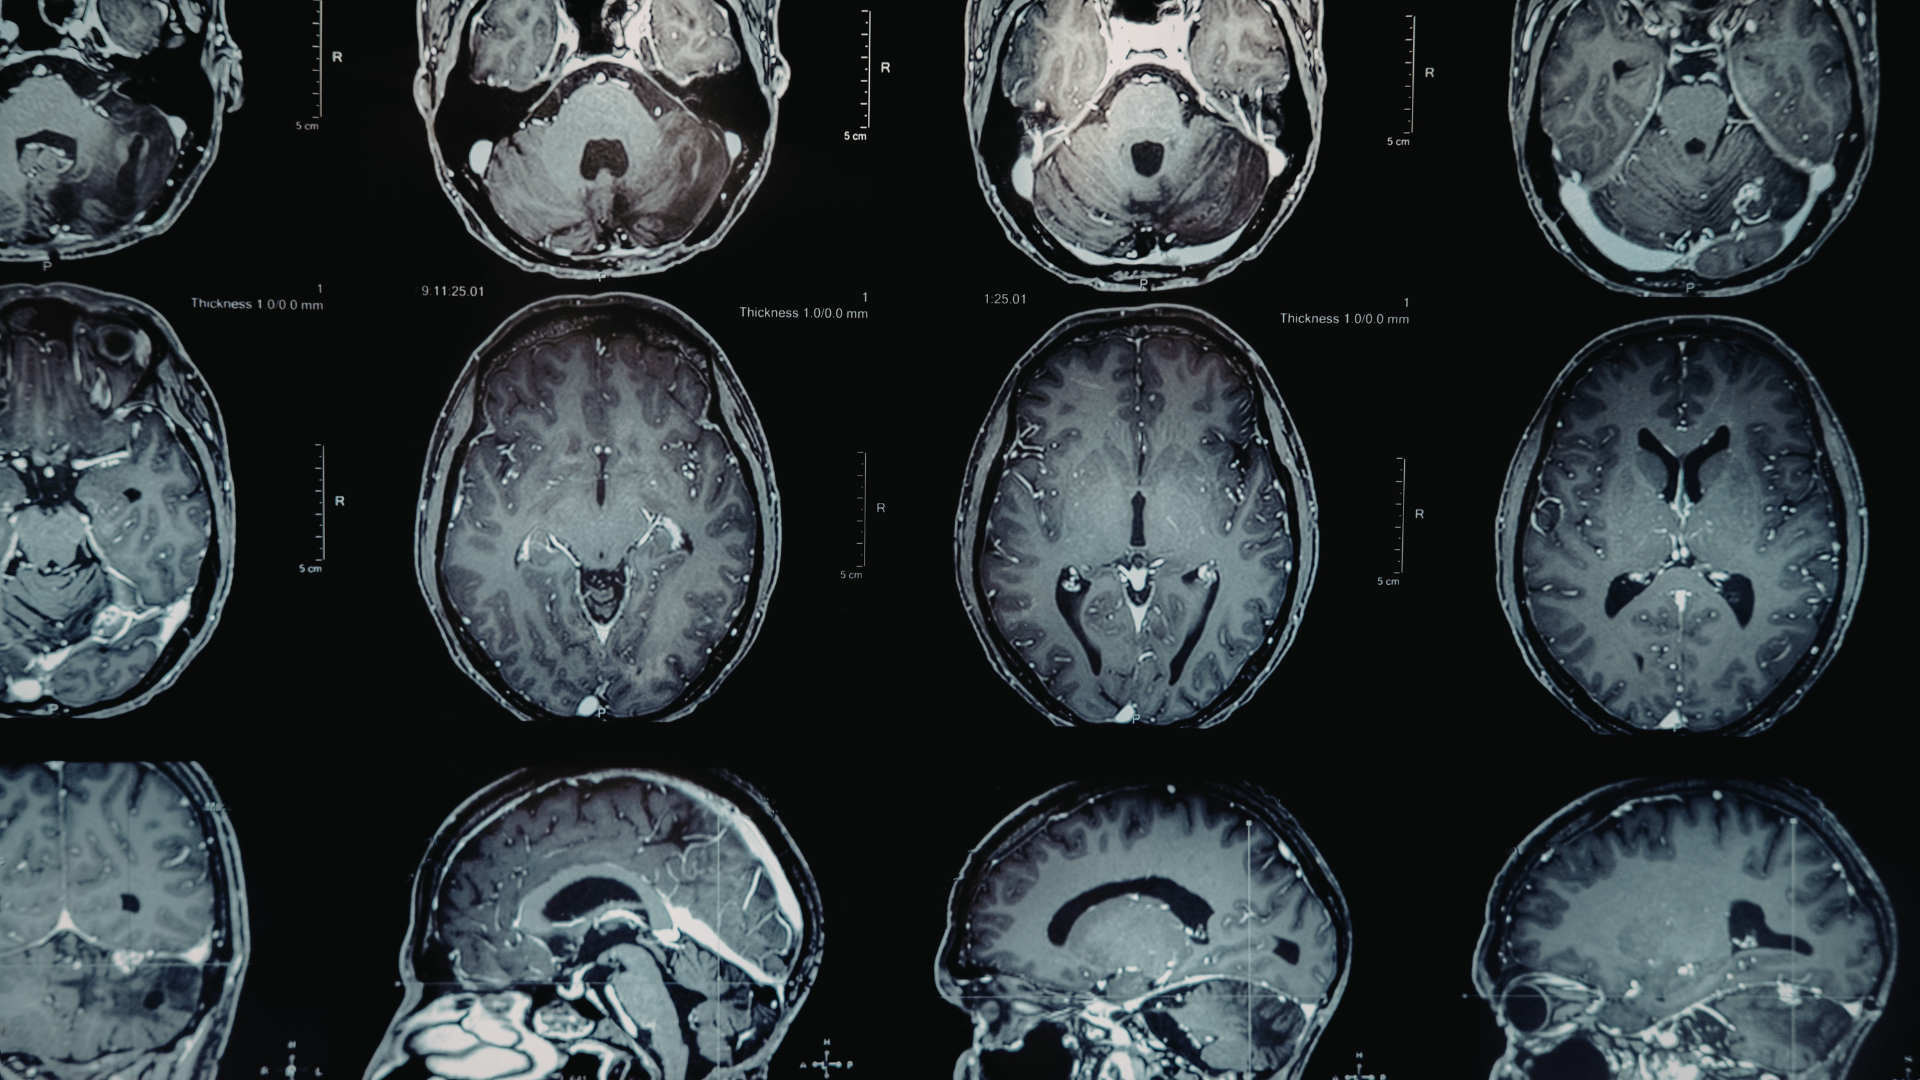

Tiểu não (cerebellum) là một phần của não sau, nằm ở vị trí bên dưới thùy chẩm và phía sau thân não. Đây là vùng đảm nhiệm việc điều chỉnh các chuyển động có chủ đích, phối hợp hoạt động giữa các bộ phận cơ thể và duy trì sự thăng bằng trong quá trình vận động.

Trong giải phẫu học, tiểu não có hình dạng gần giống một quả óc chó với nhiều nếp gấp nhỏ. Cấu trúc này giúp tiểu não xử lý một lượng lớn thông tin cảm giác và vận động từ nhiều cơ quan khác nhau.

Tiểu não nằm trong hố sọ sau, dưới thùy chẩm của đại não và phía sau thân não. Bên trên tiểu não được che phủ bởi lều tiểu não. Nhờ vị trí này, tiểu não có thể thu nhận và xử lý thông tin từ nhiều hệ thống như thị giác, thính giác, tiền đình và cảm giác sâu từ các cơ và khớp.